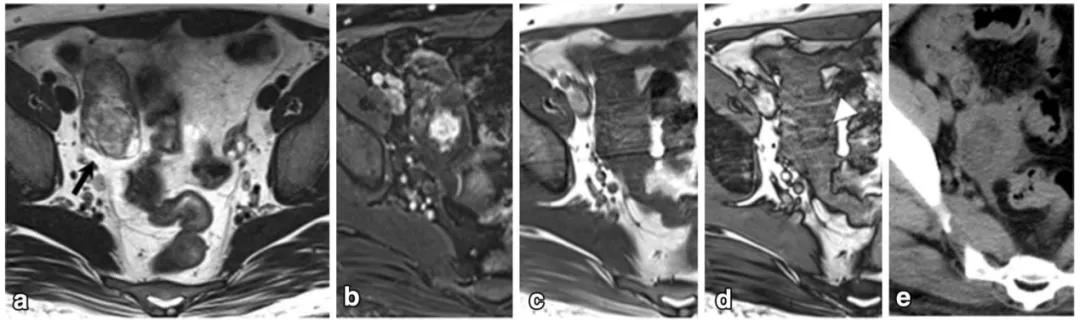

女,75 岁,浆液性癌。CA-125 升高。双侧卵巢不规则肿物,与腹膜结节分界不清,T2WI 呈不均匀稍高信号(图 a),DWI 呈不均匀高信号(图 b),CT 显示肿物内钙化(图 c)。箭头显示左侧髂血管旁转移淋巴结。

女,22 岁,无性细胞瘤。乳酸脱氢酶及碱性磷酸酶升高。T2WI 示右侧卵巢分叶状肿物(图 a),DWI 呈高信号(图 b),增强扫描明显强化(图 c)。箭头显示肿物内可见纤维血管分隔。

女,12 岁,卵巢 Burkitt 淋巴瘤。双侧卵巢肿物,T2WI 信号稍高(图 a),DWI 呈高信号(图 b),增强扫描明显强化(图 c),箭头显示肿物边缘多发囊性结节,为卵泡保留征。

女,34 岁,胃癌双侧卵巢转移瘤。T2WI 显示双侧卵巢实性肿瘤,T2WI 呈高低混杂信号(图 a),DWI 呈高信号(图 b)。